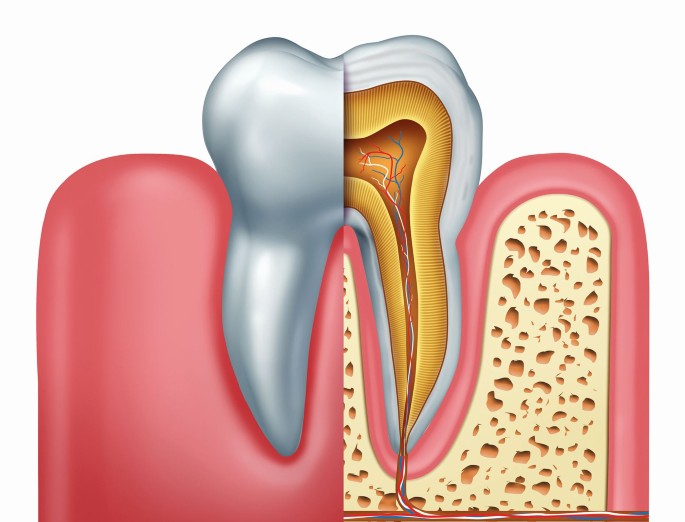

Endodontics: Essential Dental Services for Dental Health

Endodontics, the dental specialty focused on the treatment of the dental pulp and surrounding tissues, plays a crucial role in preserving natural teeth and maintaining oral health. This branch of dentistry offers a variety of dental services tailored to address both common and complex dental issues. In this article, we will explore the key services provided by endodontists, highlighting their importance for patients seeking effective dental care.

Virtually Painless Root Canal Treatment (RCT)

One of the most well-known dental services in endodontics is root canal treatment (RCT). Contrary to popular belief, modern RCT is virtually painless thanks to advancements in techniques and anesthesia. Endodontists use localized anesthesia and sedation options to ensure that patients experience minimal discomfort. This allows for a more relaxed experience, making RCT a viable solution for saving infected or damaged teeth.

Post-Endodontic Restorations Dental Services

Once endodontic treatment is complete, restoring the tooth's function and appearance is essential. Endodontists often collaborate with general dentists to implement effective post-endodontic restorations. Options such as cast posts and fiber posts provide the necessary support for the tooth, allowing it to withstand everyday chewing forces.